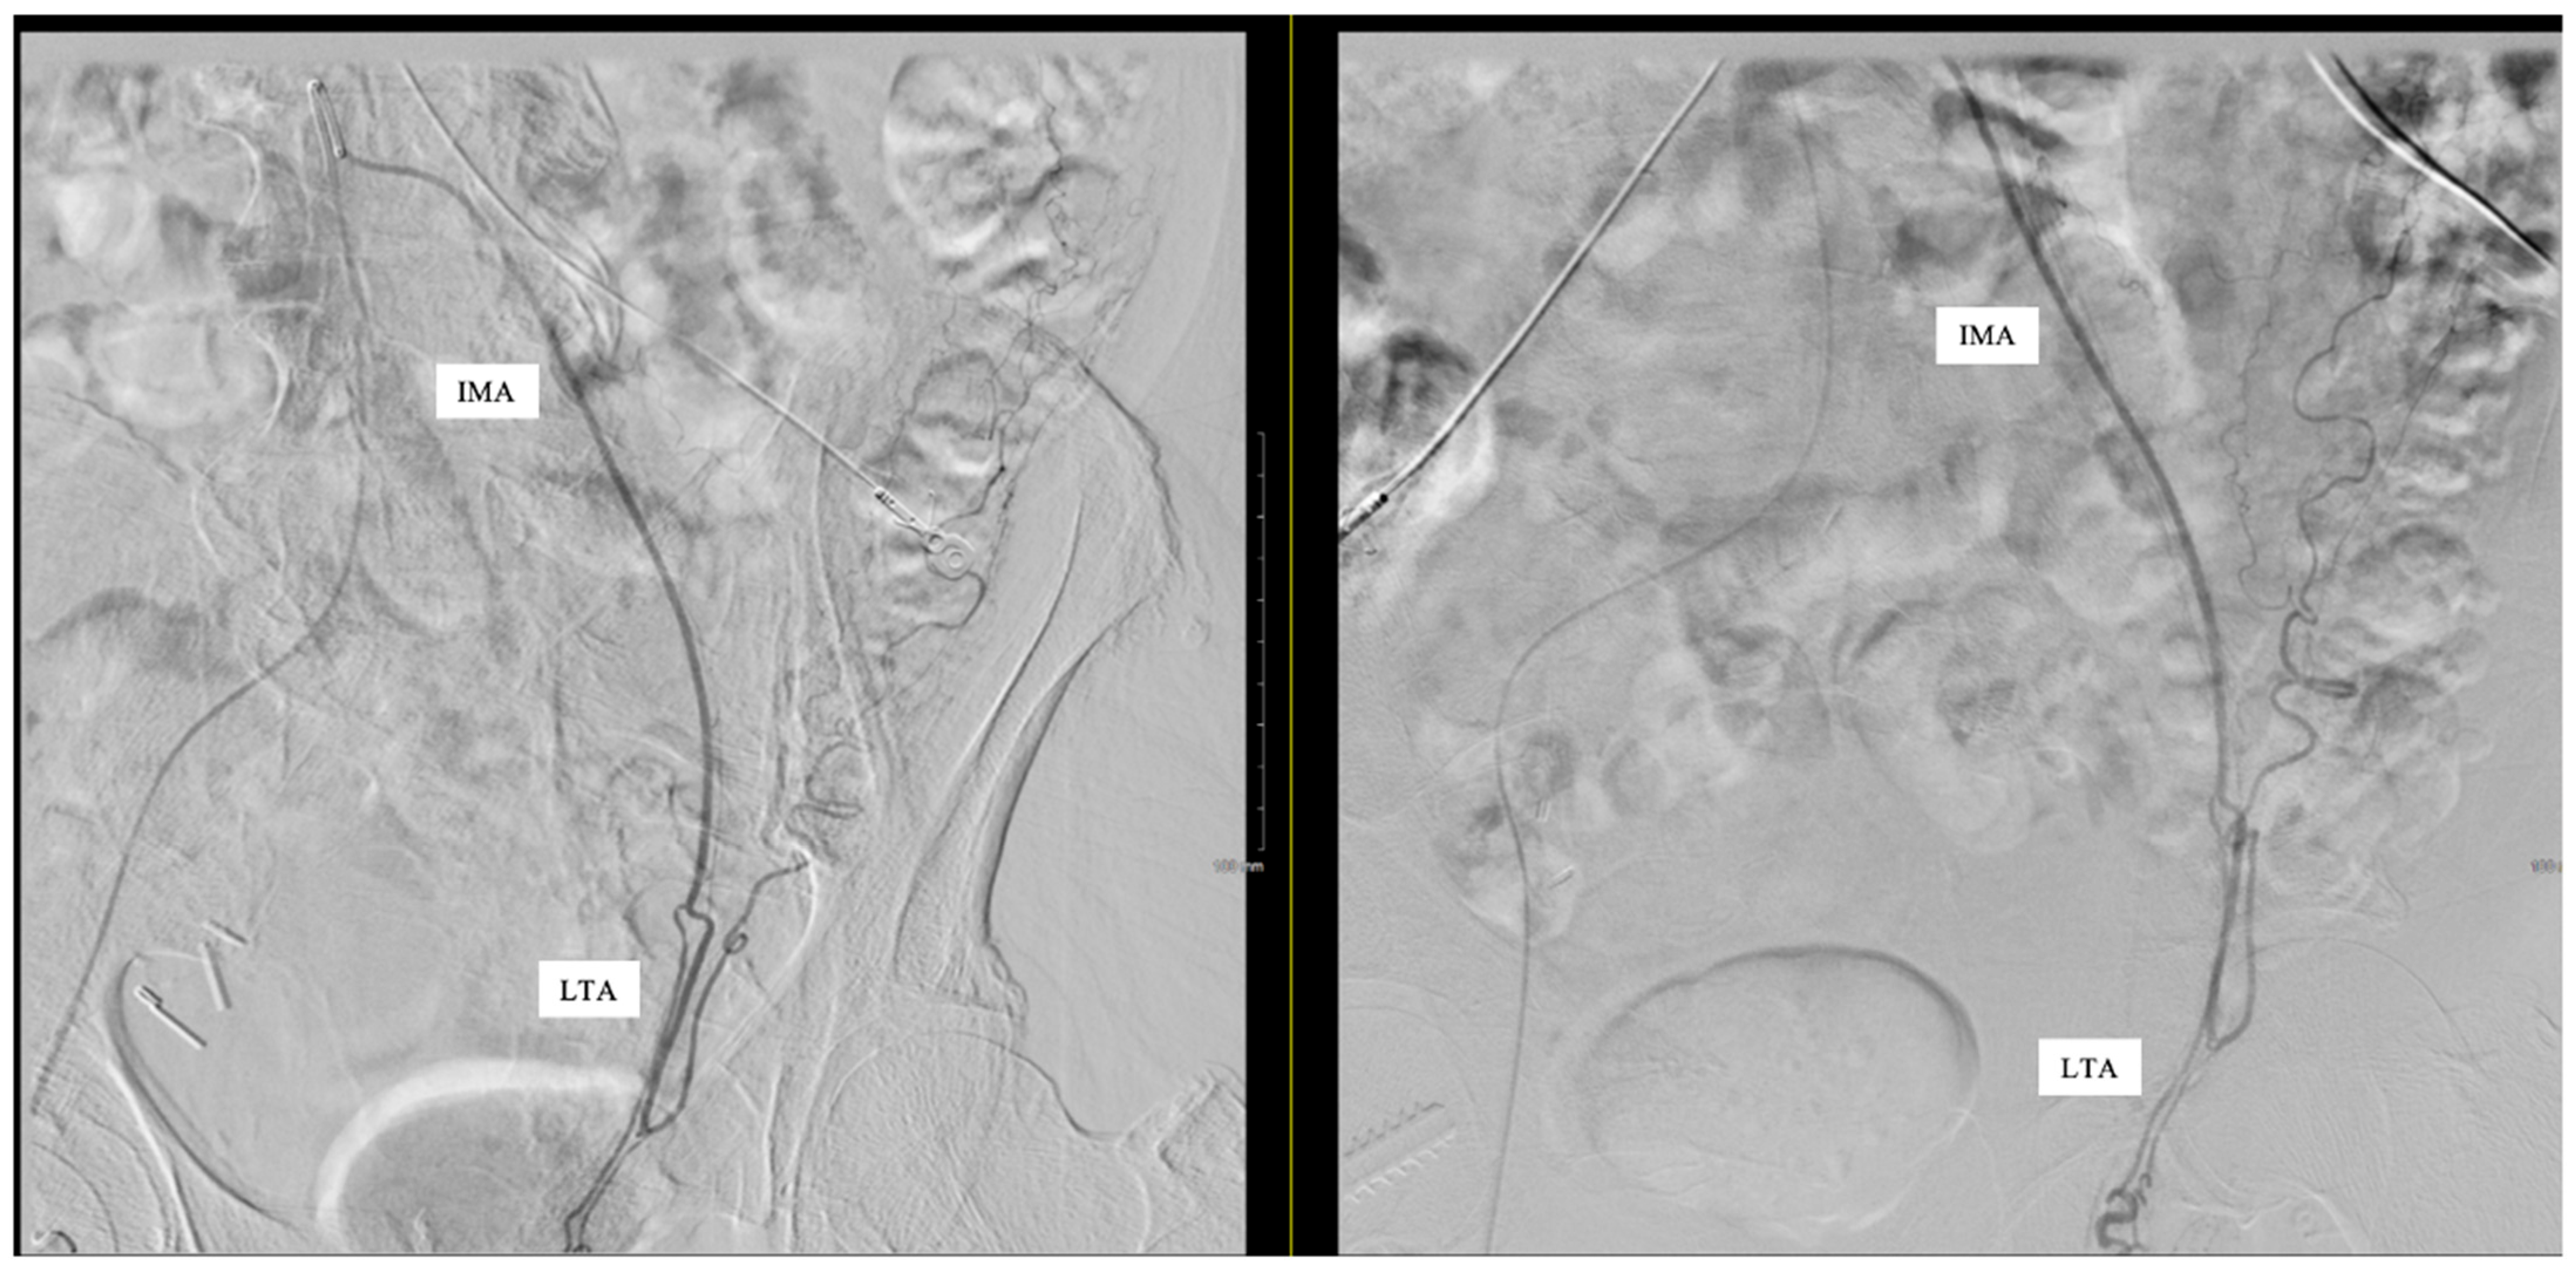

Subselective catheterization of the IMA was performed, and an angiogram demonstrated an aberrant LTA, shown in Figure 1. The sigmoidal branch was also identified; however, the superior rectal branch was absent from the IMA, as shown in Figure 2. Additionally, no active extravasation was identified. Selective catheterization of the artery supplying the sigmoidal distribution was performed, and Gelfoam embolization was performed prophylactically due to previous bleeding episodes involving the sigmoid distribution on the prior CT angiography (CTA). Postembolization arteriograms demonstrated sufficient occlusion.

Figure 2.

Left testicular artery (LTA) originating from the inferior mesenteric artery (IMA). No superior rectal branch was present.